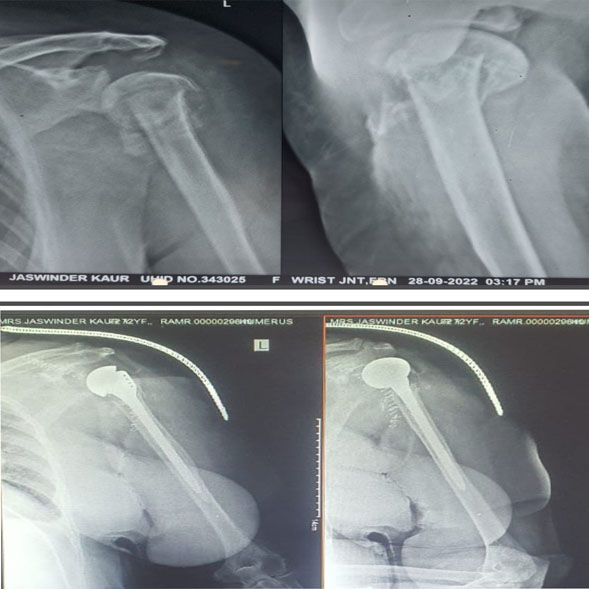

Shoulder replacement surgery is most commonly used for severe degenerative joint disease (osteoarthritis) or rheumatoid arthritis of the ball-and-socket joint. When the smooth surfaces (cartilage) of the ball and socket become rough, they rub against each other rather than glide. This rubbing causes pain and stiffness that limits daily activities, as well as interferes with sleep. Other indications that justifies shoulder replacement are severely communited fracture of proximal humerus which cannot be reconstructed and avascular necrosis of humeral head. A shoulder replacement is performed to alleviate shoulder pain. It also helps to improve the range of motion of your shoulder joint, which also improves your function and the quality of your life.

Where only the ball (humeral head) is replaced with metal stem and head.

Shoulder replacement is performed in the hospital with the help of an experienced, specialized surgical team. The procedure generally takes 2 hours. Afterwards patients stay in the hospital for 3-4 days. To get to the shoulder joint an incision is made on the front of your shoulder. After exposing the shoulder joint, the damaged ends of the bone (humerus and glenoid) are removed. The bone is prepared for the replacement with the artificial joint. The artificial joint is made of metal, usually a titanium or a cobalt-chrome alloy. For a standard shoulder replacement the stem is placed inside the humerus bone. The glenoid component is made of a special plastic (polyethylene). The glenoid is cemented into place. Not all patients require a glenoid component and the final decision to use a glenoid component is made during the surgery. For reverse shoulder replacements the ball is secured to the socket with a press-fit and supplemented with screws. The humeral stem is then press-fit or cemented into place. A high-strength plastic then is placed to act as a spacer between the stem and the ball.

This is for 4 to 6 weeks depending on the type of shoulder replacement surgery. Standard total shoulder replacements and partial replacements require a sling for 4 weeks after surgery. Reverse total shoulder replacements require a sling for 6 weeks.